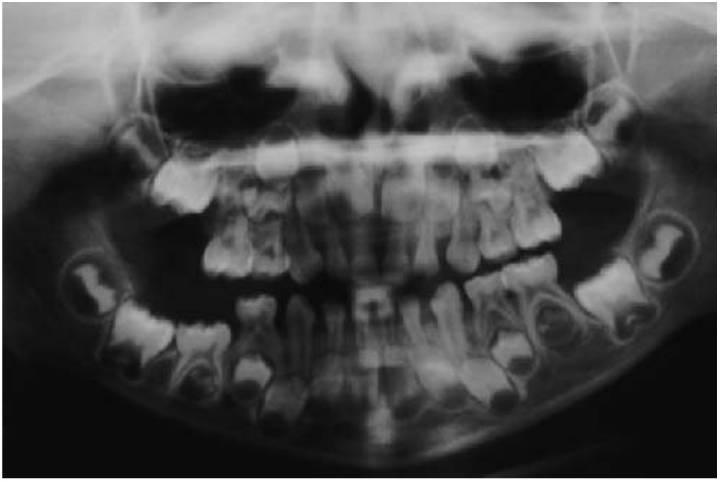

Los pacientes pueden presentar hinchazón facial y/o fallo en la erupción de los dientes, sobre todo de los molares mandibulares. Las radiografías revelarán radiotransparencias multiloculares, que afectan principalmente a los ángulos de la mandíbula (fig. 9.11). Una biopsia revelará células gigantes multinucleadas en un estroma tisular fibroso. Los dientes en desarrollo de la zona afectada tienden a desplazarse y no erupcionan a su tiempo. Los maxilares, así como las costillas, pueden estar afectados y la hinchazón facial refleja la afectación del hueso subyacente. En algunos pacientes, puede exponerse la esclerótica de la parte inferior de los ojos para dar el aspecto querúbico o «mirada al cielo» que le da el nombre a la enfermedad. En algunos casos, no existe una hinchazón facial discernible y el trastorno se identifica como el resultado de exámenes radiológicos rutinarios o de la planificación de un tratamiento ortodóntico, o bien de la erupción tardía de los dientes.

El cuadro progresa en la adolescencia y se va resolviendo más adelante, de forma que en la tercera o cuarta décadas de la vida no se encuentran cambios radiográficos. En algunas familias, el número de varones afectado supera al de las mujeres debido a la escasa penetrancia en las mujeres, y debe tenerse en cuenta en el asesoramiento genético. Un subgrupo de pacientes con querubismo con una mayor afectación presenta radiotransparencias multiloculares que afectan al maxilar y la mandíbula. En los casos leves puede bastar la realización de revisiones periódicas y en los casos más graves puede requerirse la reducción quirúrgica si al paciente le angustia su aspecto.